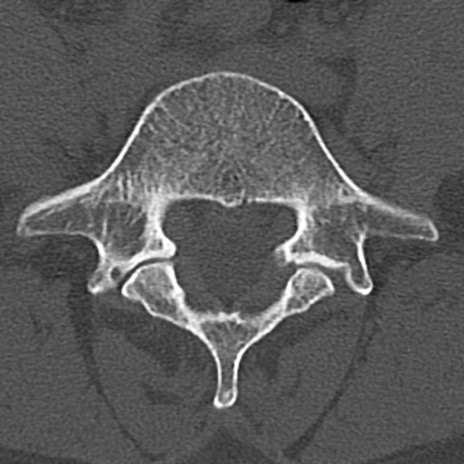

腰椎CT

横断像と矢状断像